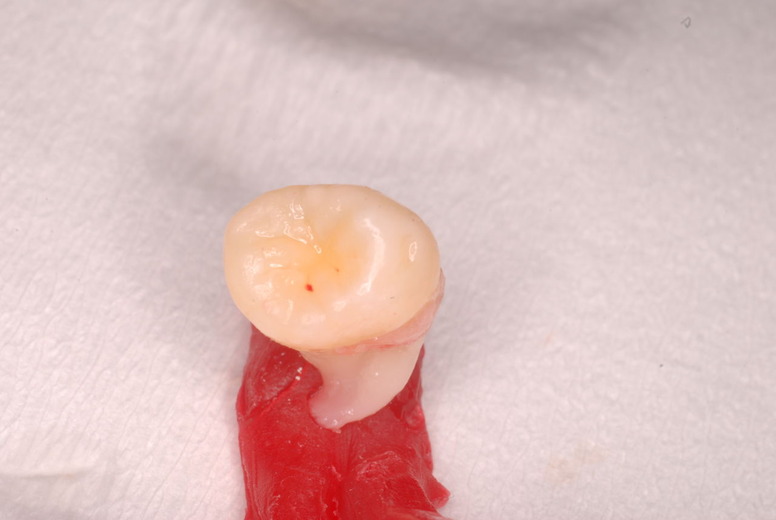

写真左下の親知らずが痛くなり抜歯しました。その後歯茎を除去して虫歯を露出させる処置を二回ほどしています。

レントゲンでは小さいですが、こう言う虫歯が一番怖いのです。

治療の成功率は極めて悪くすぐ再発しやすいのです。